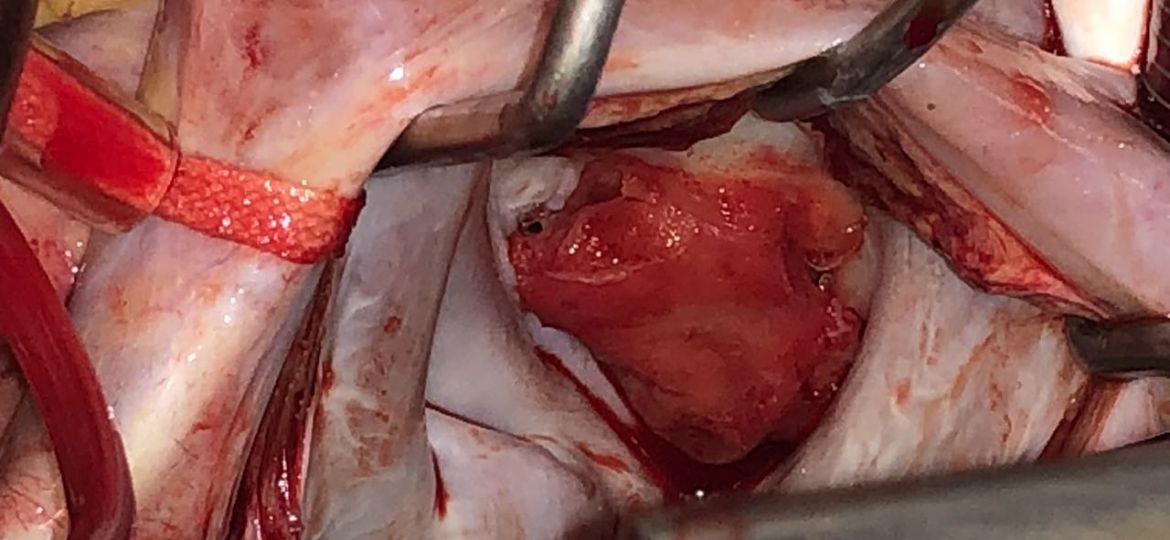

O traumatismo cardíaco relacionado a agressões e acidentes de trânsito é uma das principais causas de morte em todo o…

O aneurisma do ventrículo esquerdo é definido como uma porção do ventrículo que se torna fina e dilatada, com margens…

A endocardite bacteriana aguda é uma doença com alto risco de morbidade e mortalidade, embora desde a década de 1960…